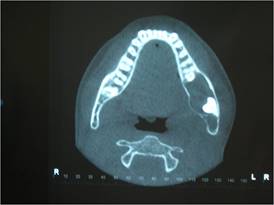

A cone-beam volumetric tomography was ordered to better assess the extent of the lesion, which showed the lesion's anatomical boundaries and relationships (Fig. 2).